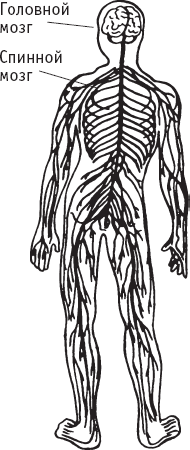

Периферическая нервная система

Спинной мозг состоит из собственных нейронов, которые передают сенсорные и двигательные импульсы. Кроме того, в нем располагаются покрытые миолиновой оболочкой аксоны, которые отвечают за передачу сигналов в обоих направлениях между тканями и головным мозгом.

Периферическая нервная система

Периферическая нервная система включает 12 пар черепных нервов, которые входят в мозг и выходят из него и связаны с областями головы, лица и шеи, и 31 пару спинномозговых нервов, которые входят и выходят через отверстия между позвонками. Эти нервы проводят сенсорные и двигательные импульсы в обоих направлениях между головным мозгом и тканями и органами.

В периферической нервной системе есть отделы, которые могут контролироваться сознанием, и отделы, которые сознанием не контролируются. Первые позволяют чувствовать, например, зуд в ногах посредством импульсов, которые идут от ног через спинномозговой канал в головной мозг, где этот импульс анализируется и квалифицируется как зуд. Затем головной мозг посылает импульс через спинной мозг к мышцам рук, побуждая их делать почесывающие движения.

Не контролируемые сознанием отделы регулируют бессознательные движения, например изменения сердечного ритма, частоту дыхания, деятельность желез, потоотделение. Импульсы этих отделов перерабатываются главным образом в стволе мозга, без осмысления. Например, информация о перегревании тела посылается от спинного мозга в ствол мозга, который отдает команды потовым железам выделять пот для охлаждения тела.